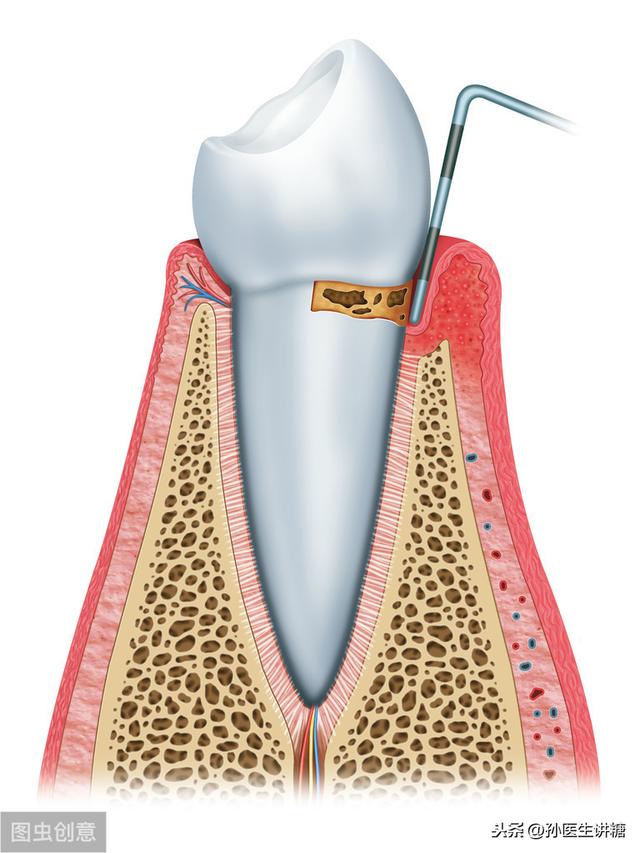

La parodontite est une maladie infectieuse chronique des tissus de soutien parodontaux causée par des micro-organismes présents dans la plaque dentaire, entraînant l'inflammation et la destruction des tissus de soutien parodontaux, principalement sous la forme deFormation de poches parodontales, perte progressive des points d'attache et résorption de l'os alvéolaireCette maladie est très répandue chez les patients diabétiques et est donc considérée comme l'une des complications chroniques du diabète.

Le diagnostic de la parodontite comprend principalement l'inflammation gingivale, le saignement, la profondeur des poches parodontales et la perte d'attache.

Elle peut être classée en trois degrés selon sa gravité :

Gingivite légère : inflammation des gencives et saignement au sondage.

Parodontite modérée avec inflammation des gencives, saignement au sondage, écoulement purulent et déchaussement léger des dents.

Dans le cas d'une parodontite sévère, l'inflammation est plus prononcée ou un abcès parodontal se produit, et la dent est plus susceptible de se déchausser.

Le diabète sucré est une maladie métabolique caractérisée par l'hyperglycémie, qui peut endommager les petits et les grands vaisseaux sanguins. Des études ont montré que les tissus parodontaux subissent des modifications de la morphologie microvasculaire, du flux sanguin microvasculaire et de la morphologie périvasculaire.

Les patients diabétiques sont sujets à des troubles de la cicatrisation des lésions. L'hyperglycémie peut être localisée dans l'activité des fibroblastes et des ostéoblastes du tissu terminal circulant, de sorte que la matrice osseuse et la production de collagène sont réduites, ce qui entraîne une réduction de la capacité de réparation et de régénération du parodonte et d'autres parties, tout en activant la collagénase, ce qui entraîne la destruction du collagène, la perte de l'os alvéolaire, le déchaussement et la perte de la dent.

Tout d'abord, la parodontite est la destruction des tissus de soutien des dents (gencive, membrane parodontale, os alvéolaire et dentine) due à l'infection par la plaque dentaire et à divers autres facteurs - formation de poches parodontales avec inflammation, perte d'attache et résorption de l'os alvéolaire et, dans les cas les plus graves, perte de dents. La parodontite, en tant que maladie inflammatoire très répandue, est susceptible de menacer la santé systémique de l'hôte.

- Le diabète sucré affecte principalement l'apparition et l'évolution de la parodontite, en particulier chez les patients dont le contrôle glycémique est insuffisant, où l'inflammation des tissus parodontaux est plus importante, les bords gingivaux sont rouges et gonflés avec une hyperplasie granulomateuse, des saignements et des abcès parodontaux sont susceptibles de se produire, et il y a une destruction rapide de l'os alvéolaire, conduisant à des poches parodontales profondes et à un déchaussement des dents.